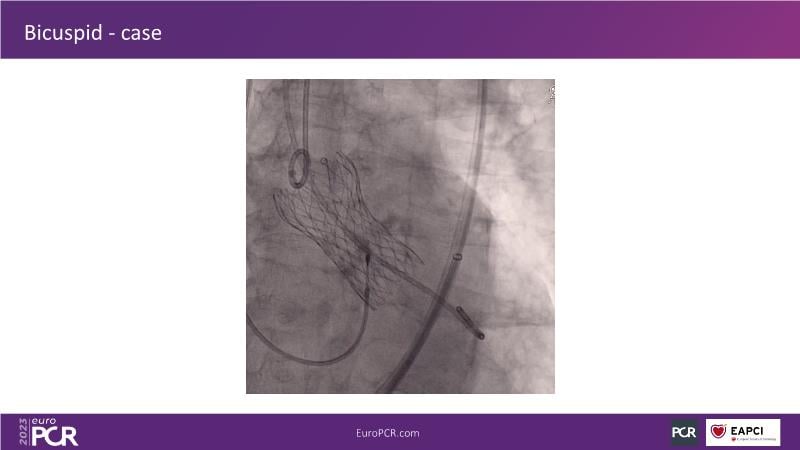

Discover the key factors to consider in selecting the optimal valve and implant technique for transcatheter aortic valve implantation (TAVI) to achieve optimal procedural outcomes. Gain insights into the impact of device choice and implantation technique on coronary access following TAVI and learn valuable strategies for tailoring your TAVI technique to complex scenarios, including bicuspid aortic valves, large and calcified anatomies, and ensuring coronary access.

- To learn how to tailor your TAVI technique to complex situations: bicuspid aortic valves, large, calcified anatomies and coronary access